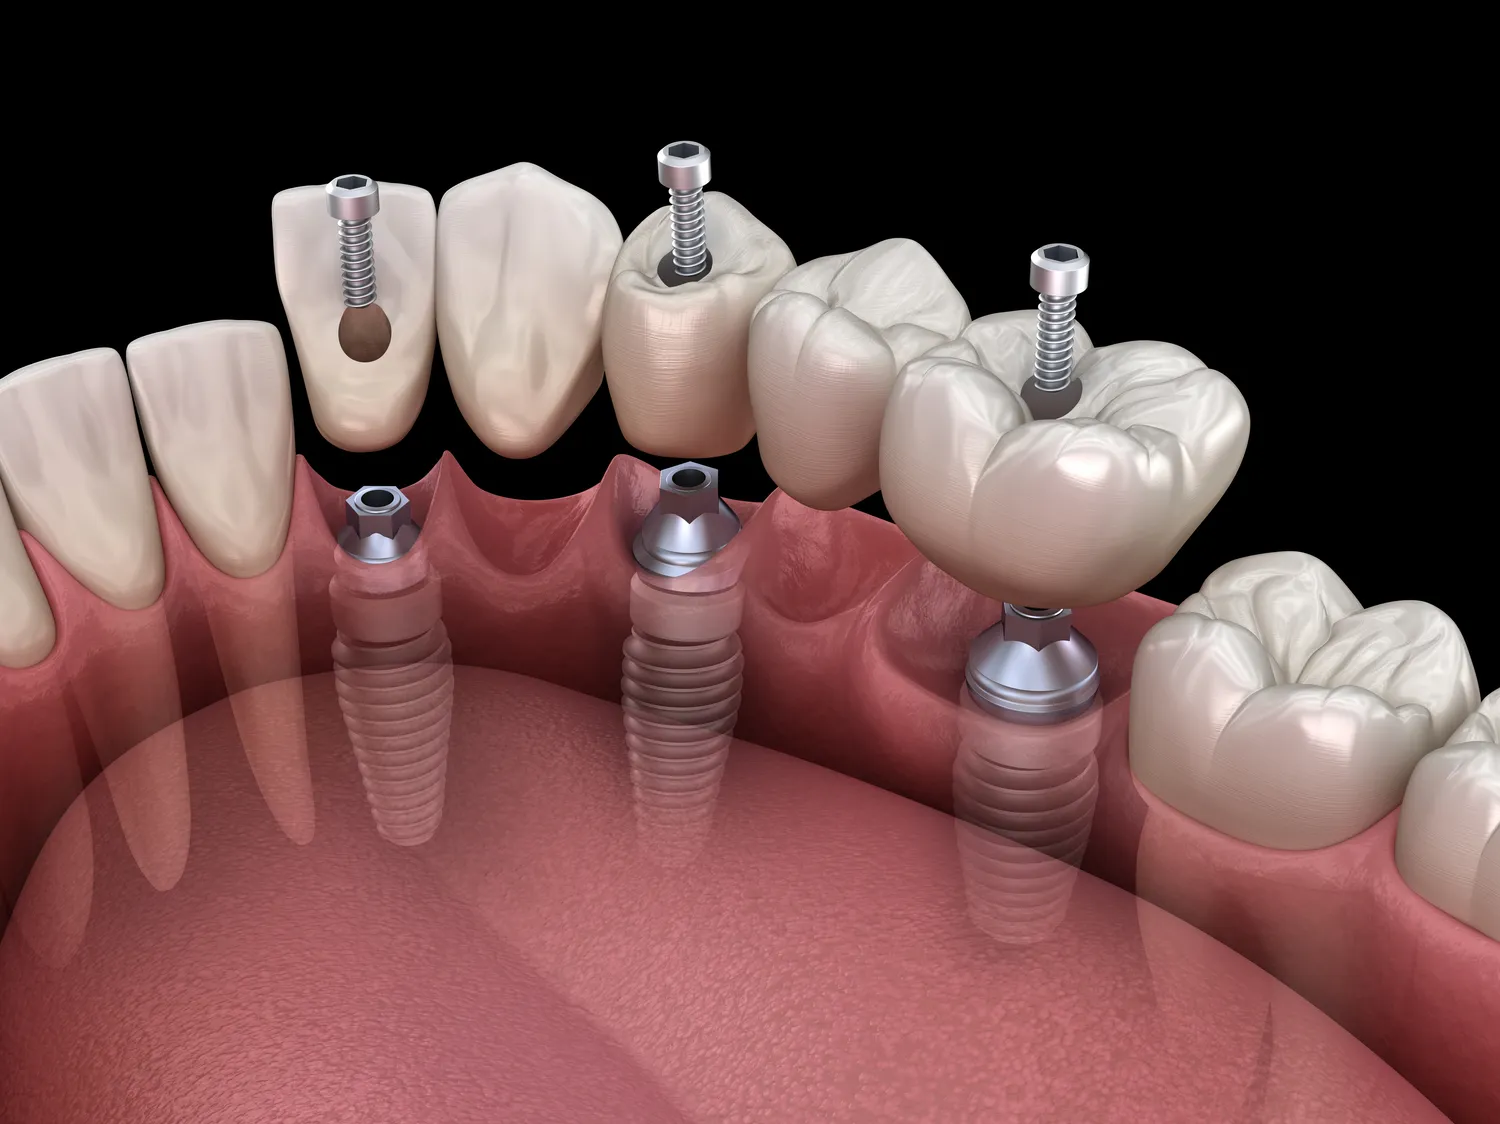

Proces leczenia implantologicznego w Turcji zazwyczaj rozpoczyna się od konsultacji ze specjalistą stomatologiem, który oceni stan zdrowia pacjenta oraz zdecyduje o najlepszym planie leczenia. Po przeprowadzeniu niezbędnych badań diagnostycznych, takich jak zdjęcia rentgenowskie czy tomografia komputerowa, lekarz przystępuje do zabiegu wszczepienia implantu. Zabieg ten odbywa się zazwyczaj w znieczuleniu miejscowym i trwa od jednej do kilku godzin w zależności od skomplikowania przypadku. Po wszczepieniu implantu następuje okres gojenia trwający zazwyczaj od kilku tygodni do kilku miesięcy, podczas którego implant integruje się z kością szczęki. Po zakończeniu procesu gojenia pacjent wraca do kliniki na kolejne wizyty kontrolne oraz na wykonanie korony protetycznej. Cały proces może trwać od kilku tygodni do kilku miesięcy w zależności od indywidualnych potrzeb pacjenta oraz rodzaju zastosowanego implantu.